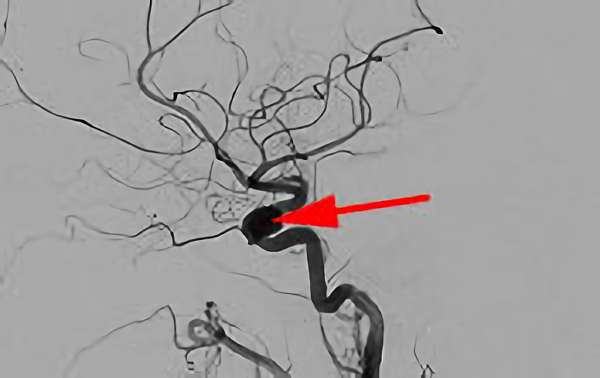

No.1631 手術前